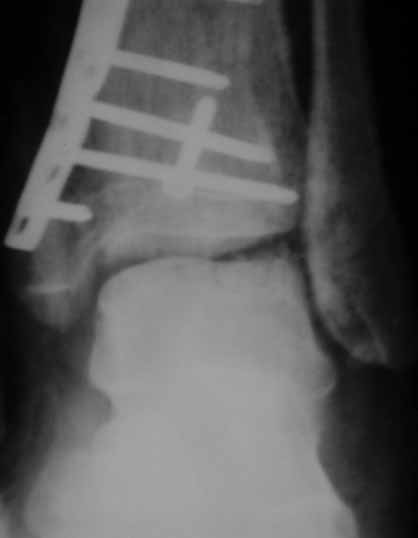

Извиняюсь пропал - оперировал "пилон". В форуме не хотел обсуждать финансовые возможности пациента. Потянул комбинированную пластину. Опыт общение с пластиной "крест" есть - не очень понравилось - слишком много места занимает, даже с учетом обрезаний лишнего. Сделал доступ огибающий медиальную лодыжку спереди. В переднем крае оказался достаточно крупный отломок - удалось зафиксировать винтом. Деффекта кости не оказалось.